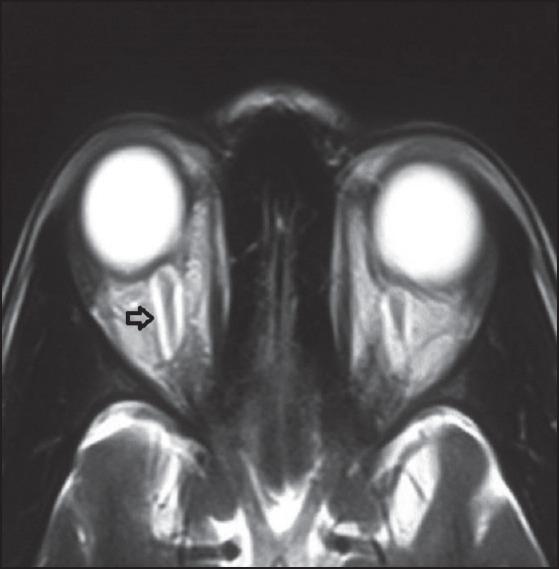

Idiopathic intracranial hypertension (IIH) is a disorder defined by clinical criteria that include signs and symptoms isolated to those produced by increased intracranial pressure (ICP; e. g., headache, papilledema, and vision loss), elevated ICP with normal cerebrospinal fluid (CSF) composition, and no other cause of intracranial hypertension evident on neuroimaging or other evaluations. The most common signs in IIH are papilledema, visual field loss, and unilateral or bilateral sixth cranial nerve palsy. Here we report a case of IIH presenting as headache with vision loss, papilledema, complete ophthalmoplegia with proptosis in one eye, and sixth cranial nerve palsy in the other eye. Patient was managed with acetazolamide, topiramate, and diuretics. Symptoms remained static and she was planned for urgent CSF diversion procedure.